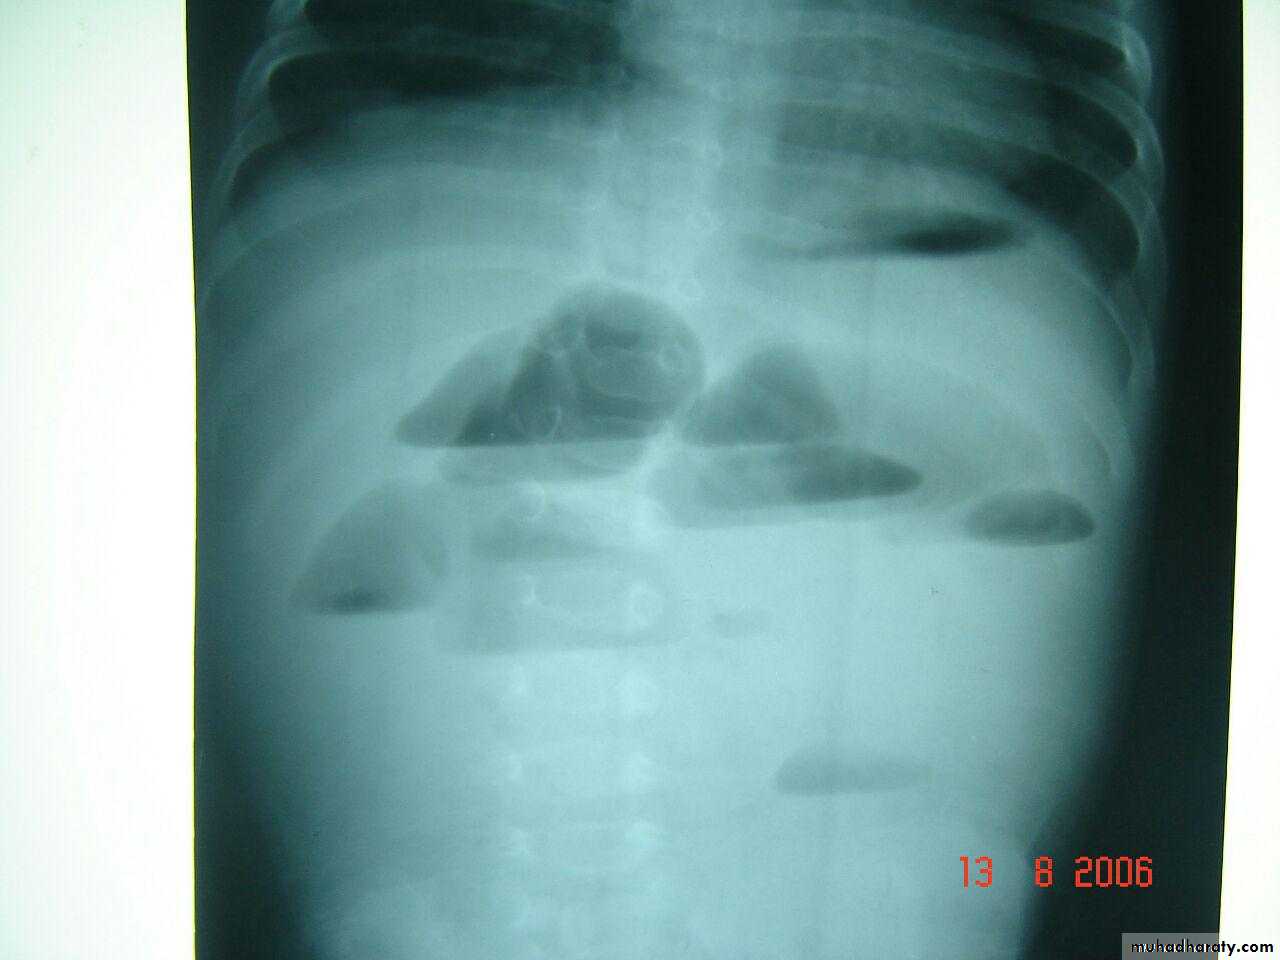

Air fluid levels of intestinal obstruction

atresia

3 bubble apperance of jujenal atresia

Double bubble apperance of dudenal atresia

Deudenal obstruction double bubble sign

Rx iv fluid , surgeryDouble bubble sign deudenal obstruction + air fluid level